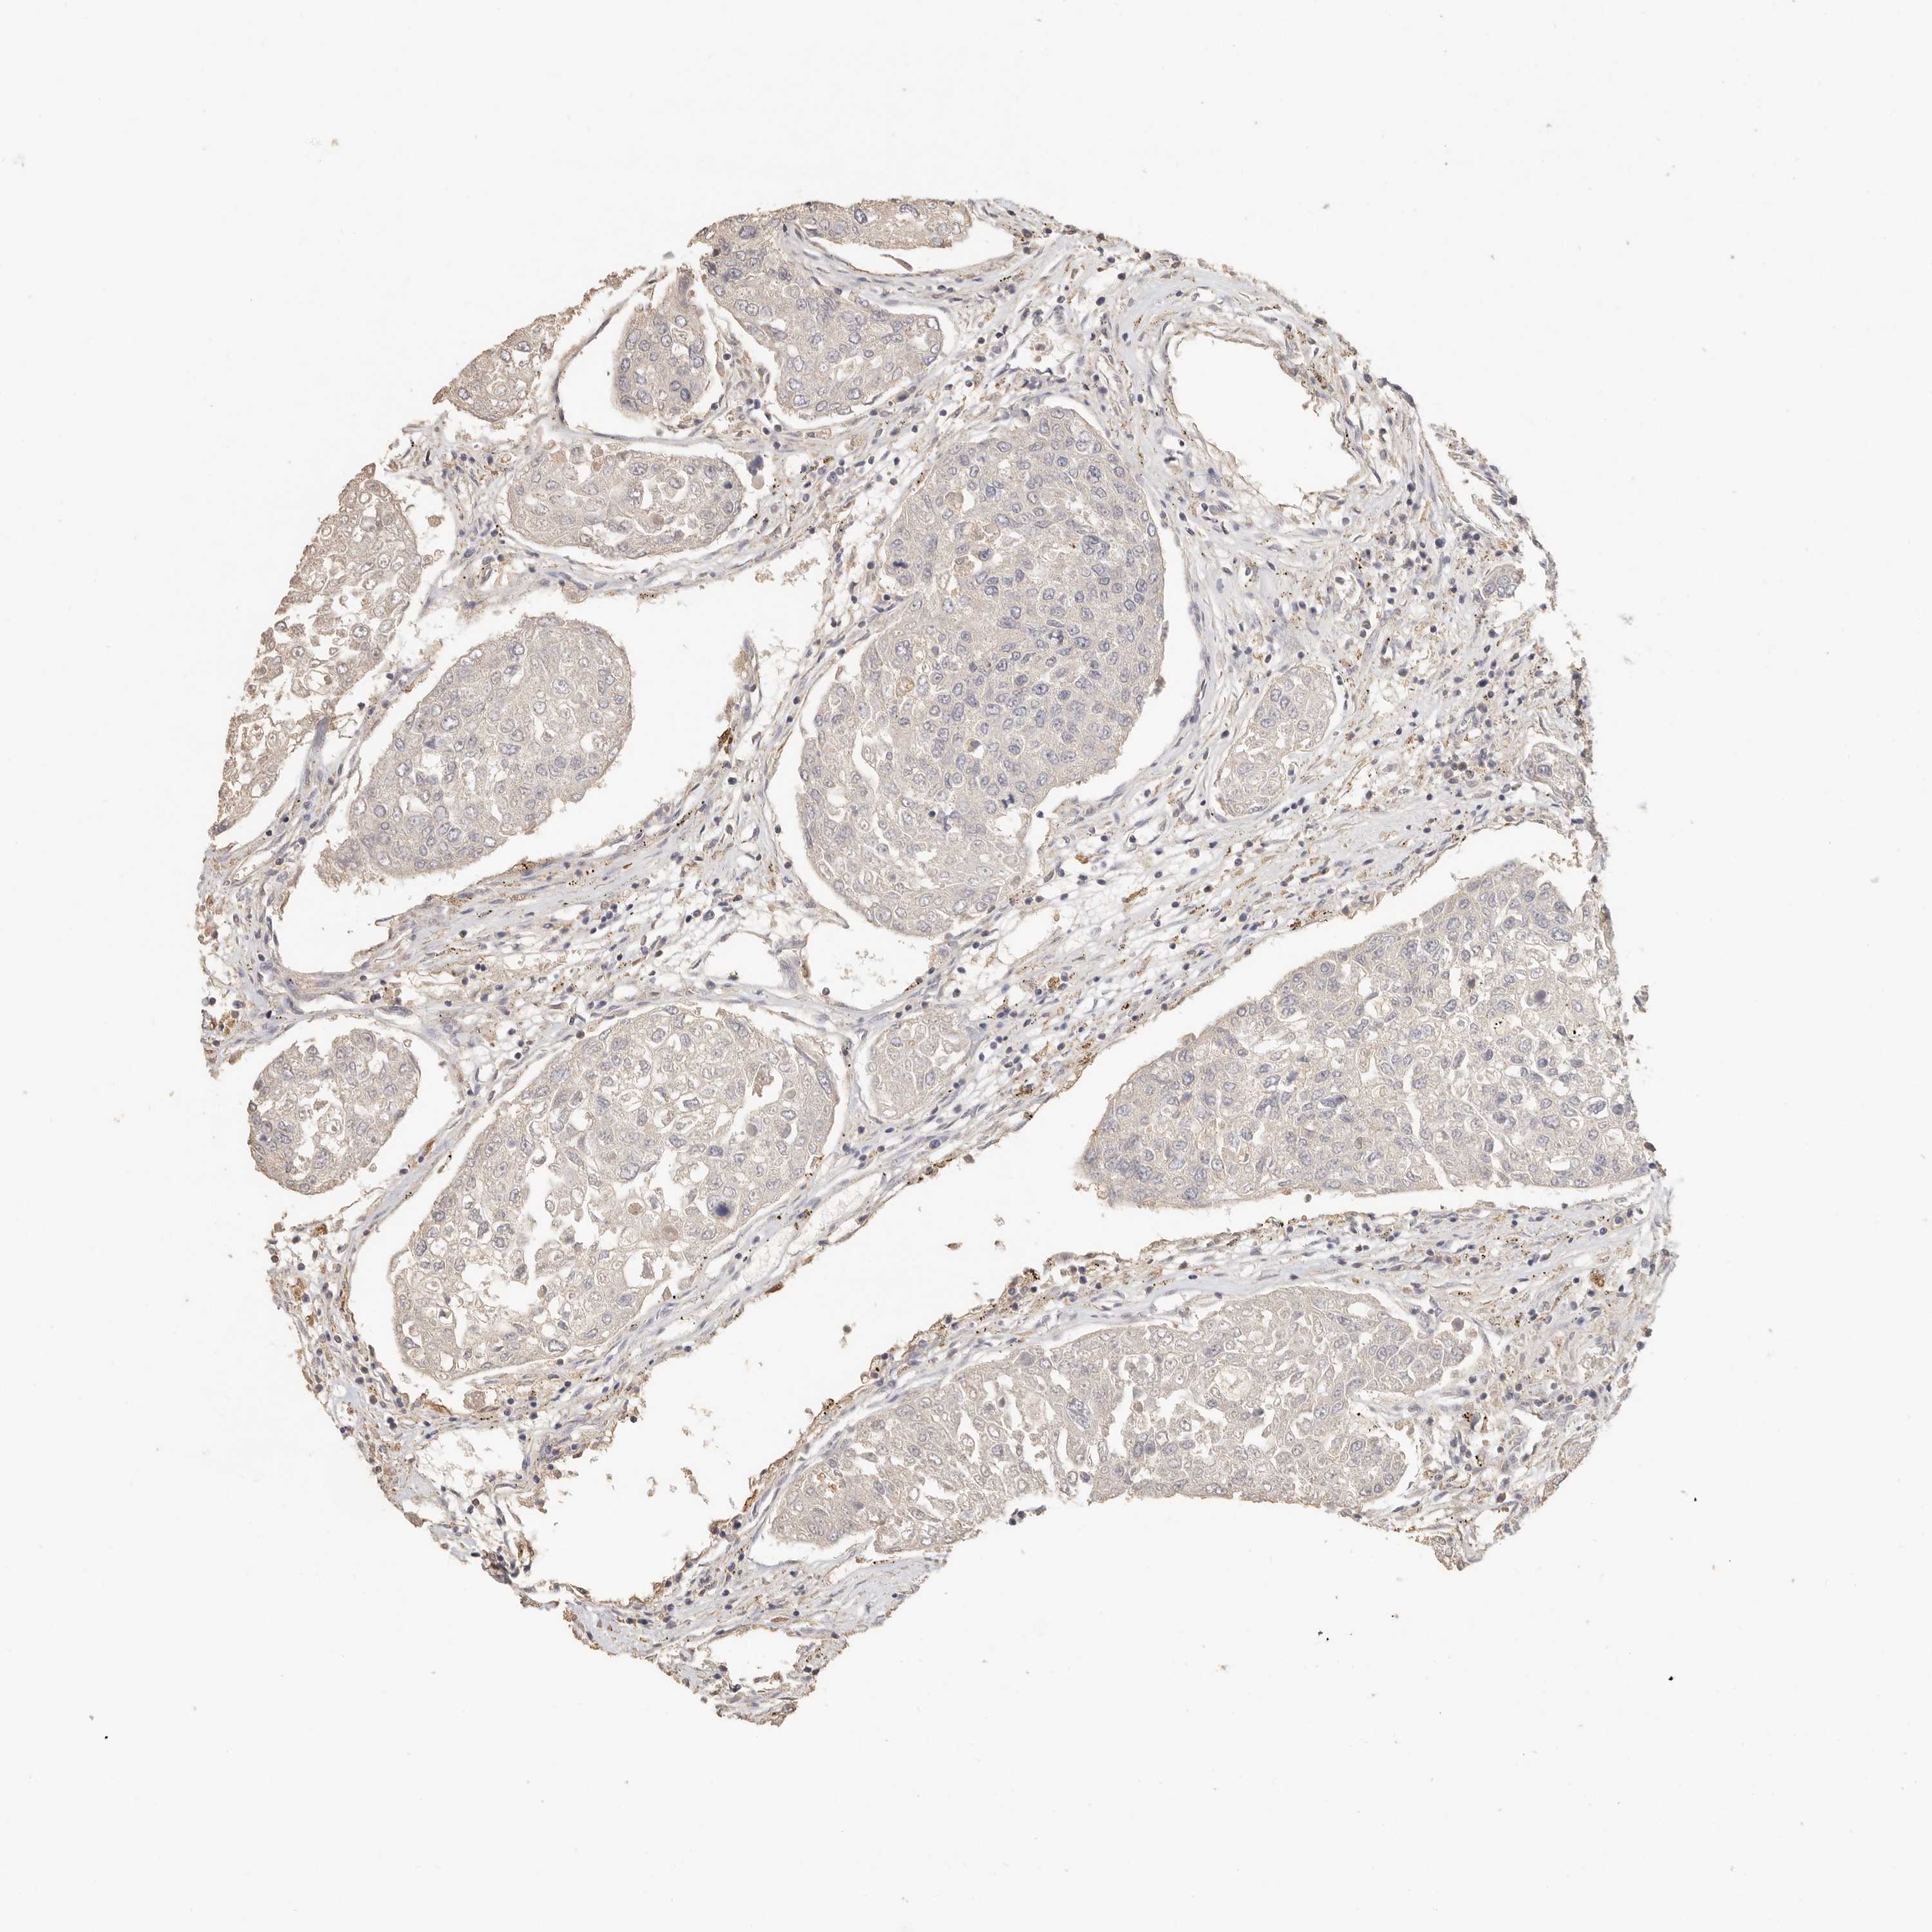

UROTHELIAL CANCER - Protein expressioni

A mouse-over function shows sample information and annotation data. Click on an image to view it in a full screen mode. Samples can be filtered based on level of antibody staining by selecting one or several of the following categories: high, medium, low and not detected. The assay and annotation is described here.

Note that samples used for immunohistochemistry by the Human Protein Atlas do not correspond to samples in the TCGA dataset.

Antibody stainingi

Antibody staining in the annotated cell types in the current human tissue is reported as not detected, low, medium, or high, based on conventional immunohistochemistry profiling in selected tissues. This score is based on the combination of the staining intensity and fraction of stained cells.

Each image is clickable and will lead to virtual microscopy that enables deeper exploration of all samples and also displays staining intensity scores, fraction scores and subcellular localization as well as patient and tissue information for each sample.

Antibody HPA026488

Antibody HPA028425

Antibody CAB011203

Staining

High

Medium

Low

Not detected

Intensity

Strong

Moderate

Weak

Negative

Quantity

>75%

75%-25%

<25%

None

Location

Nuclear

Cytoplasmic/membranous

Cytoplasmic/membranous,nuclear

Urothelial carcinoma, Low grade

Urothelial carcinoma, High grade